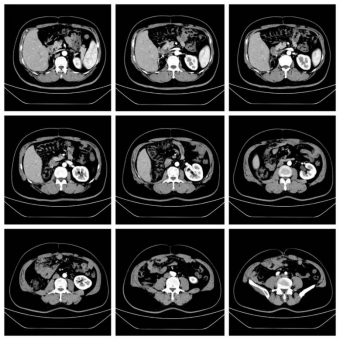

72岁男性,因体重下降2月,确诊腹膜后肉瘤10天。腹部增强CT提示左侧腹膜后巨大脂肪肉瘤,直径约30cm。

我们实施了全麻下开放腹膜后肿瘤切除术。术中发现肿瘤与结肠系膜及降结肠粘连,团队切除降结肠、部分膈肌、腹壁肌肉,横结肠和乙状结肠吻合。手术历时3个小时,出血控制在500ml以内。术后恢复良好:第2天下地活动,术后3天排气,术后1周流食,术后10天出院。